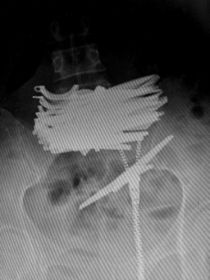

X光显示女子腹中的剪刀 X光显示女子腹中的剪刀

红网长沙5月14日讯 (潇湘晨报记者 杜方江) 5月13日上午,42岁的曲颖(化名)躺在省直中医院普外科的病床上。前一天晚上,其因腹痛被路人发现后拨打120,送往医院救治。X光片显示,其中下腹部横亘着一捆剪刀,曲颖称自己为了躲避被抓,便吞下了剪刀。

当天晚上,省直中医院急诊科对曲颖进行了抢救,随后送往普外科住院治疗,从X光片可见一捆剪刀横亘在其中下腹部,剪刀长近12厘米。医生诊断腹部肠管少量积气,未见明显液气平面和肠管扩张。